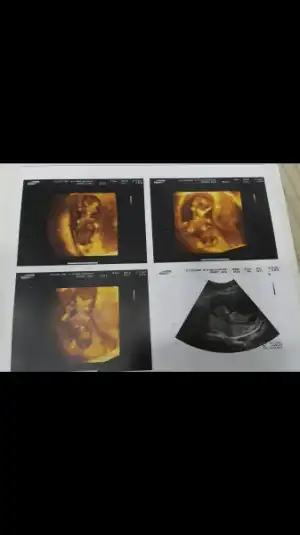

Kızlar buda benim ponçiğim bi türlü resmini koyamamıştım ama sonunda başardım. Ikili tests gunu cekilmis fotolari 11+6 idi o gun ama ultrasonda 12+3 çıķmıştı. Doktor erkege benzio demisti dikkat ettimde resimde bülüşünü gördüm ben sağ üstteki resmde